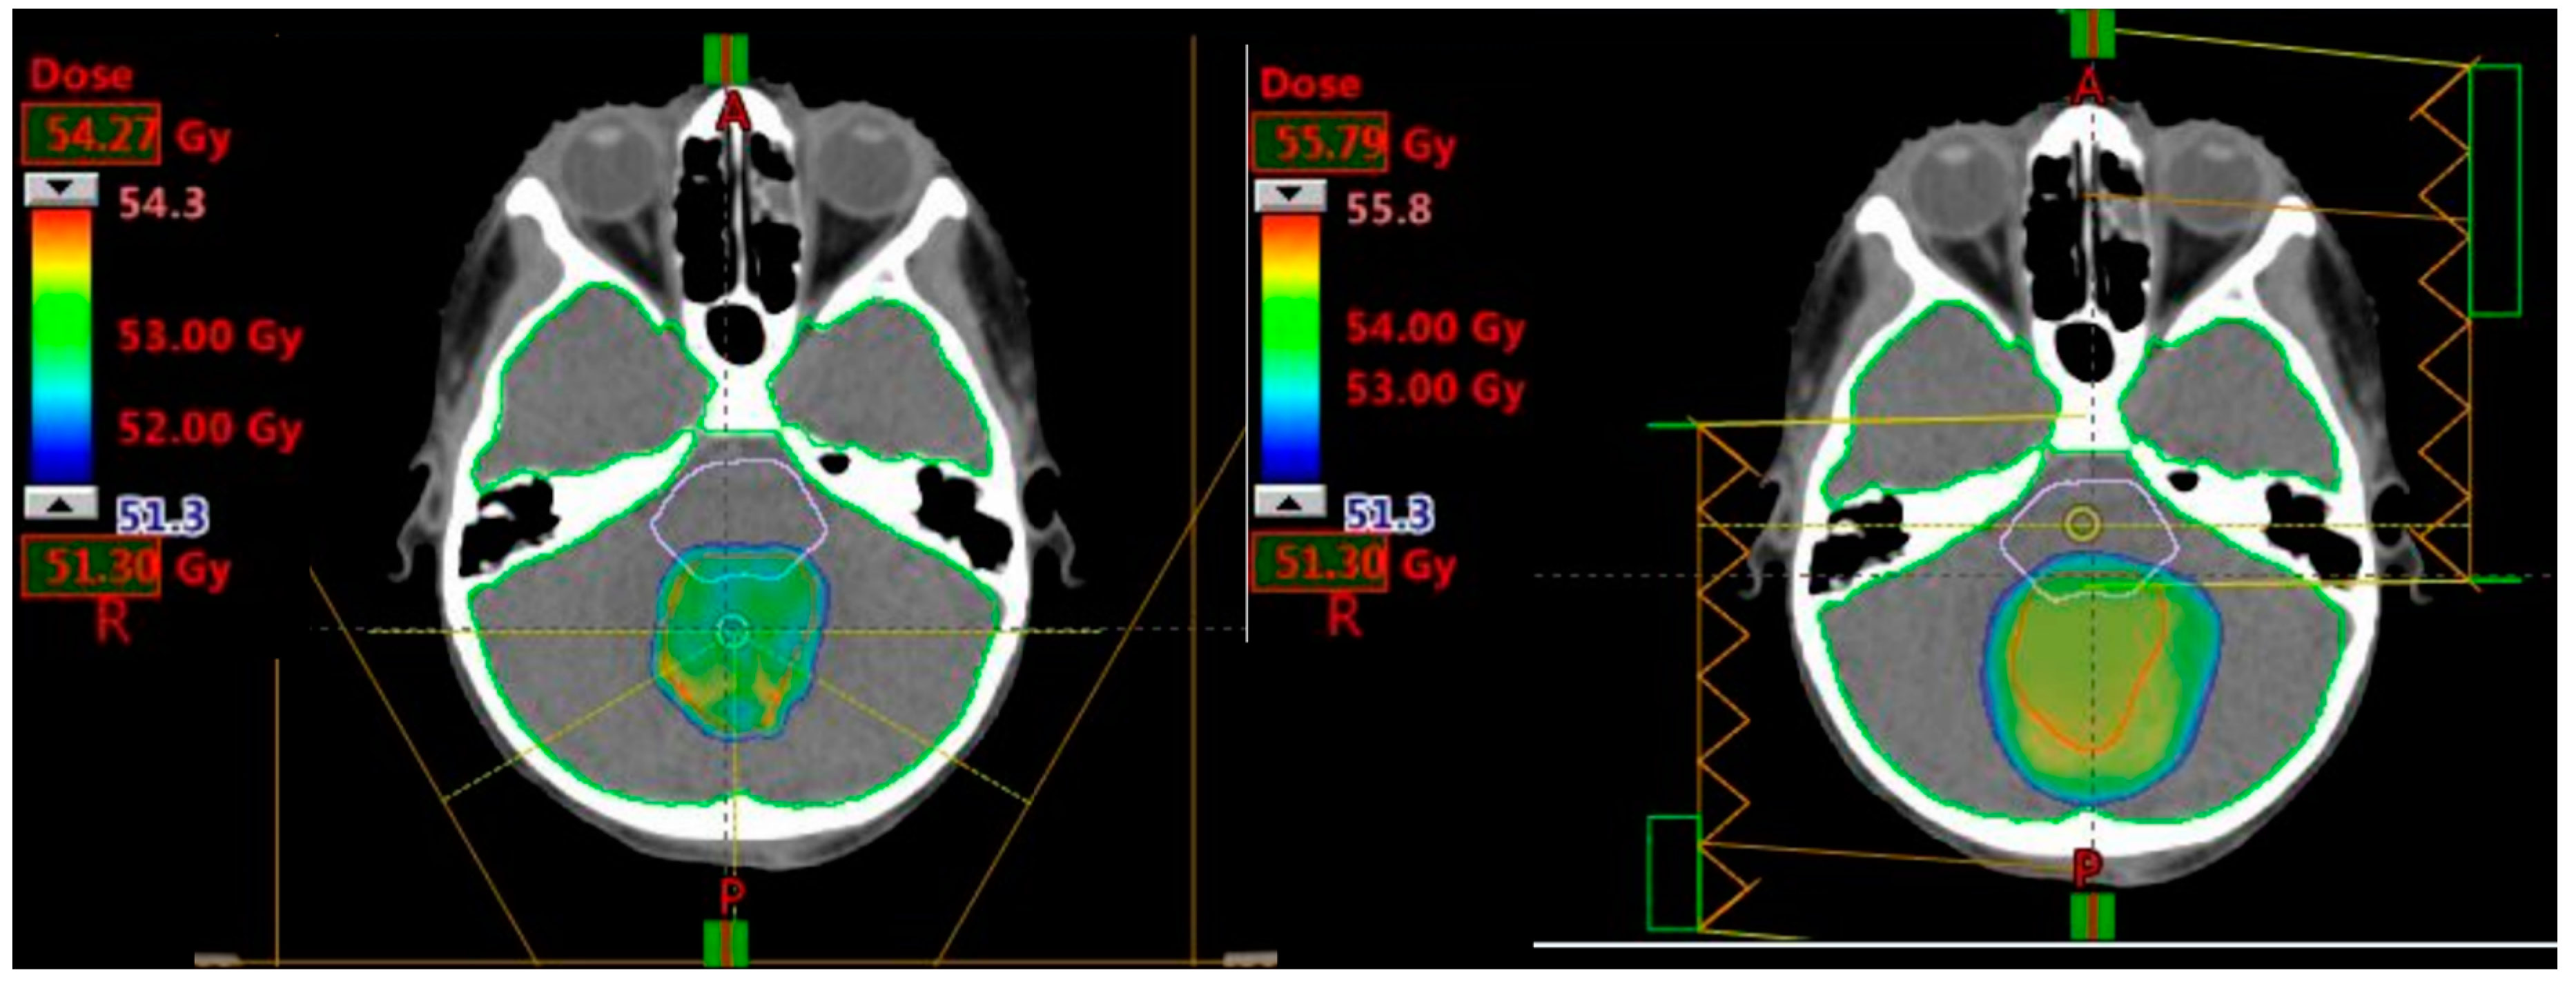

All IMRT plans were planned to deliver a prescription of 54 Gy (1.8 Gy per fraction). Five co-planar IMRT photon fields of 6 MV energy were required (gantry angles: 30, 100, 170, 240 and 310 degrees) to adequately cover the target volume (see Figure 2). IMRT plans were optimised to similarly deliver a CSI dose of 24 Gy via opposed lateral fields and a 30 Gy boost phase using a five field co-planar arrangement (see Figure 3).

Figure 2. Colourwash dose distributions and dose–volume histograms for a 5-year-old male with supratentorial ependymoma. Typical planning beam arrangements and dose–volume histograms viewed on axial and coronal CT images for intensity-modulated proton therapy (IMPT) (left ) and intensity-modulated photon radiotherapy (IMRT) (right ) plans.